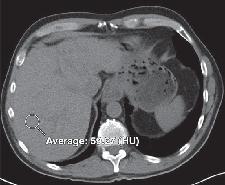

先来看一个病例:68岁女性患者,1年半前因乏力及双下肢水肿,就诊于当地医院诊断为“肝硬化”,2周前因上述症状加重。全身皮肤黏膜及巩膜轻度黄染,双手及颜面部黑色素沉着,双下肢轻度凹陷性水肿。腹部CT平扫如下图:

最后真相大白,该患者为继发性含铁血黄素沉着症。过多的含铁血黄色在肝脏沉积,导致肝脏继发的表面不光整,造成“肝硬化”的假象。我们再仔细看肝脏CT图像,肝脏密度升高,明显高于同层面脾脏、腹主动脉管腔密度。

肝脏正常密度是多少?(悄悄告诉你,45HU-65HU)。遇到肝脏密度弥漫增高的患者,我们诊断思路是什么,考虑哪些疾病?该如何鉴别诊断?